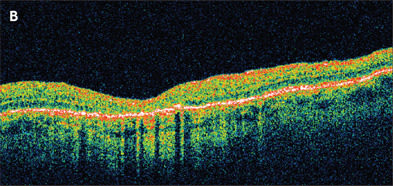

Figure 2. A. Stage 3 macular hole previtrectomy. B. Same eye 6 weeks after vitrectomy and successful closure of the macular hole.